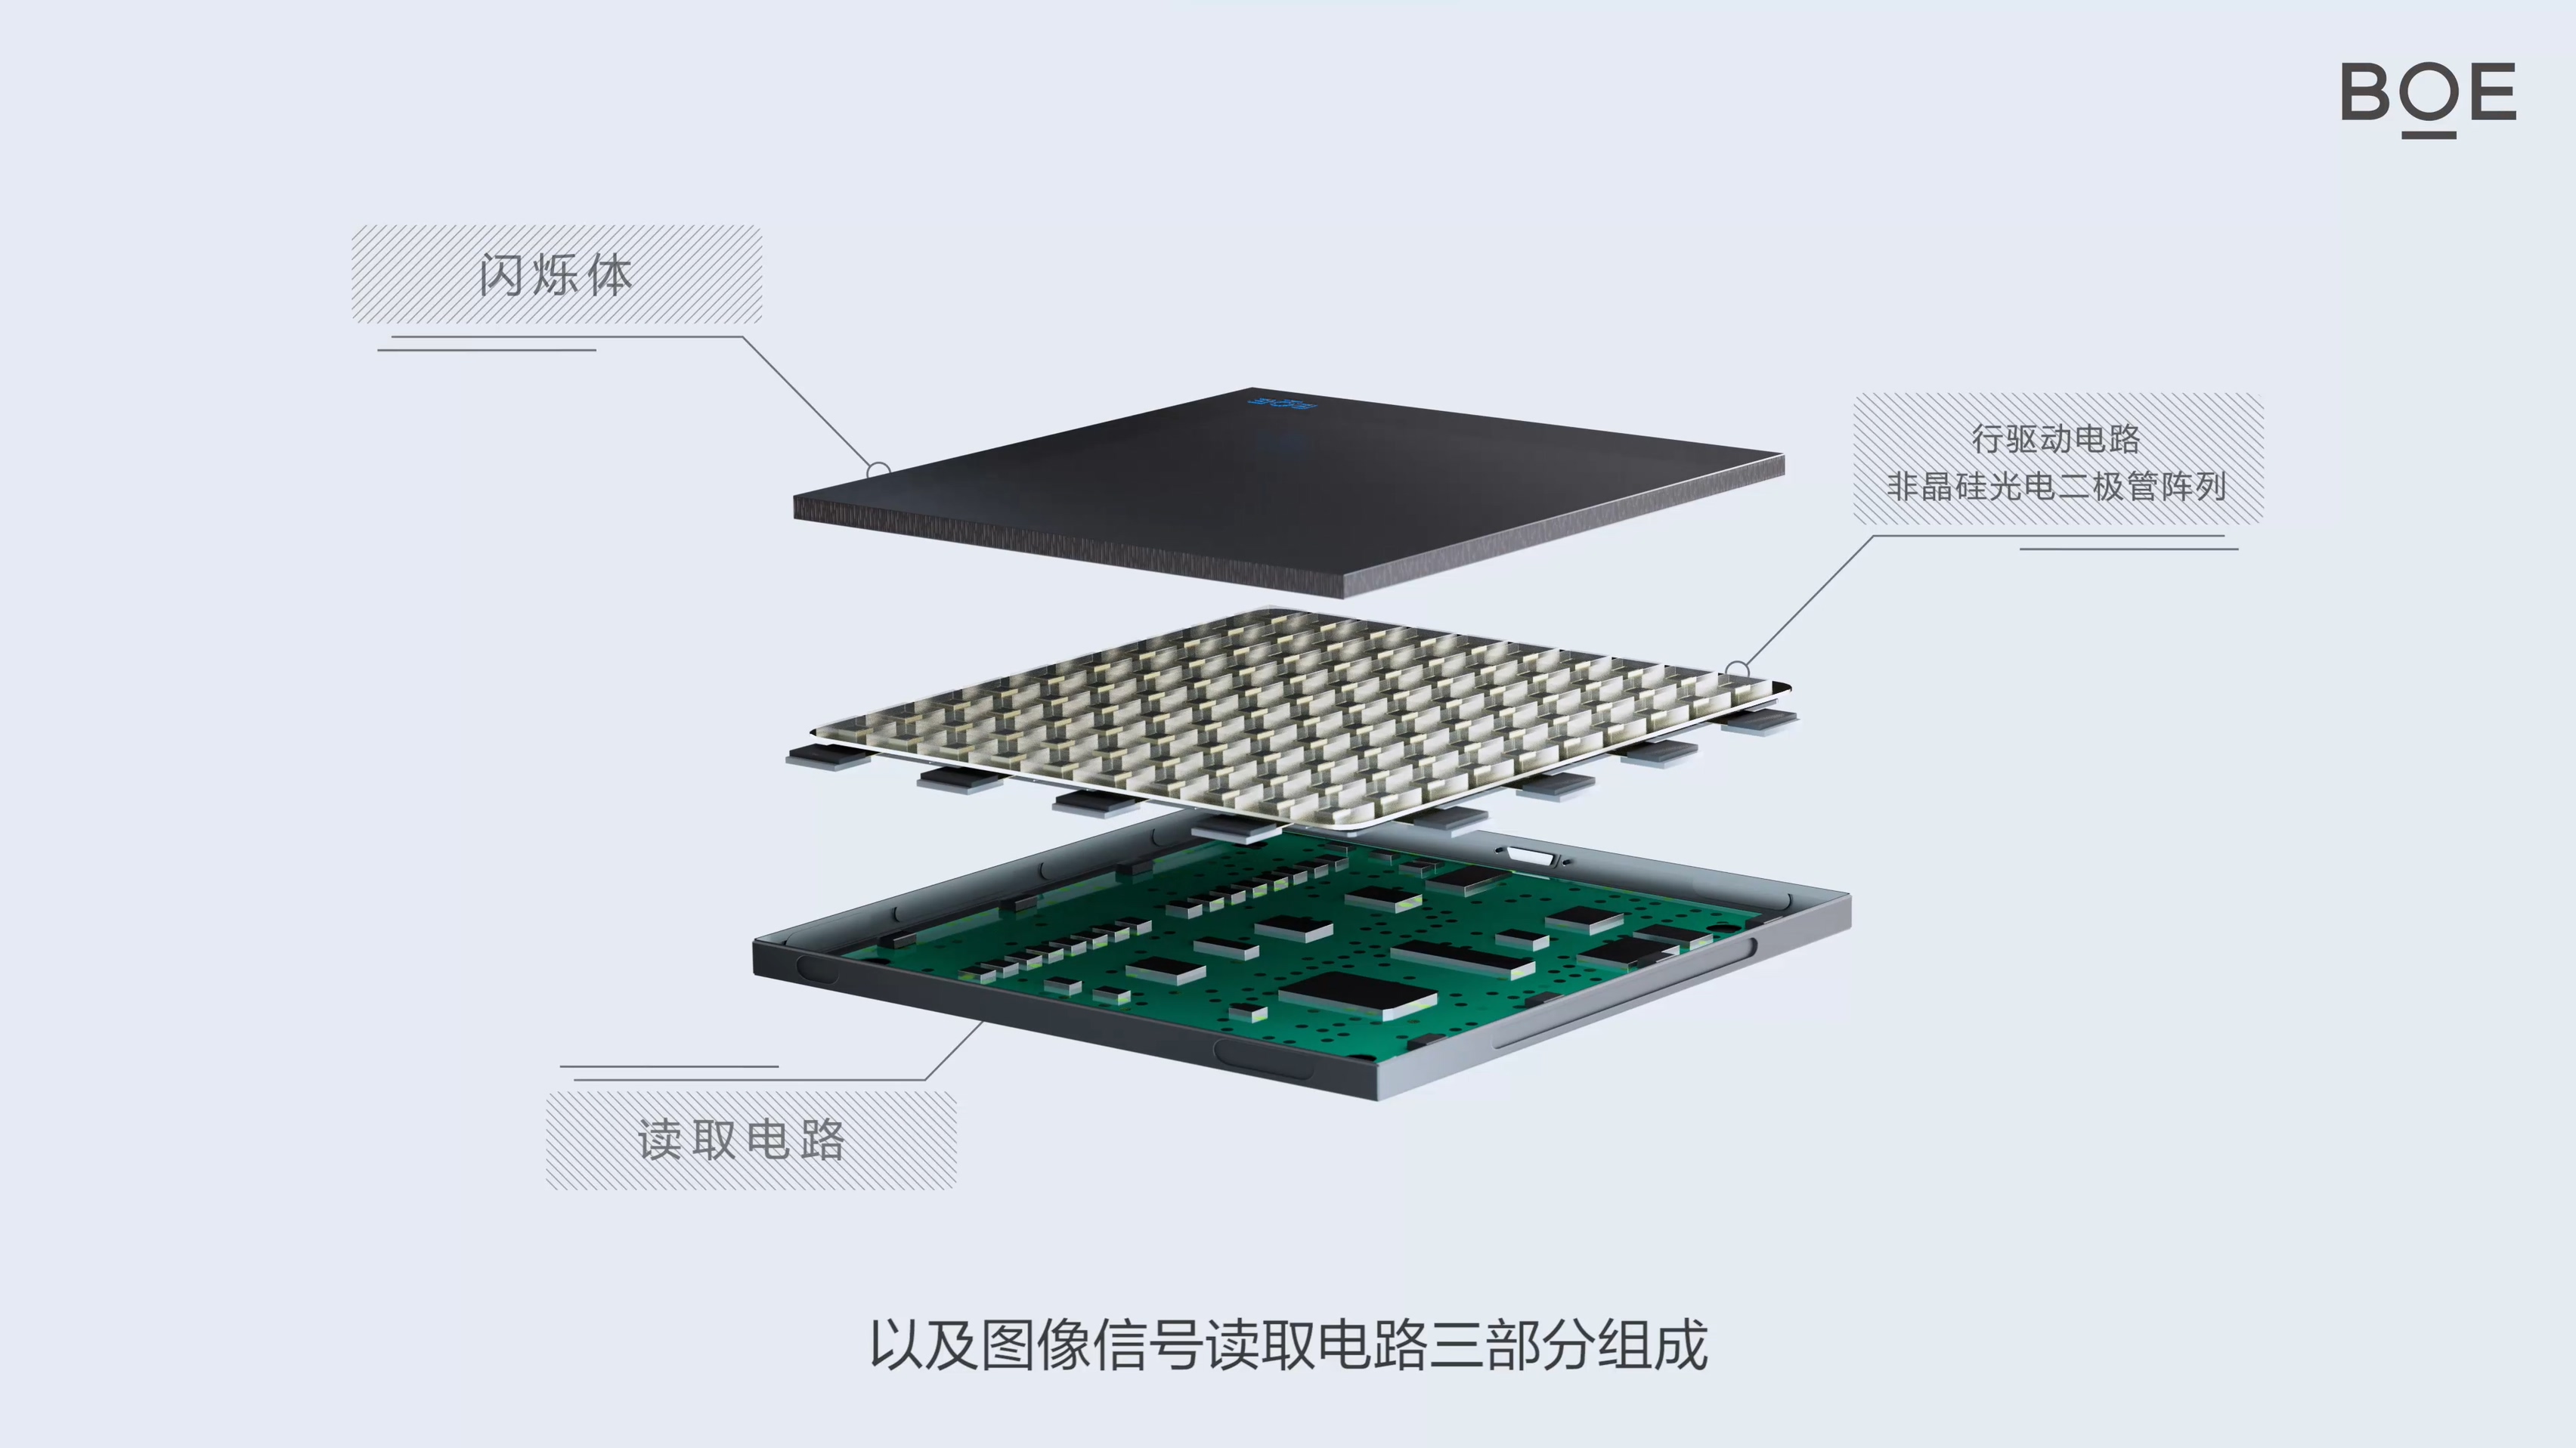

The X-ray detector backplane independently developed by BOE features low dose, high resolution, high conversion efficiency, high signal-to-noise ratio, and wide dynamic range, which can be widely used in medical and industrial fields.